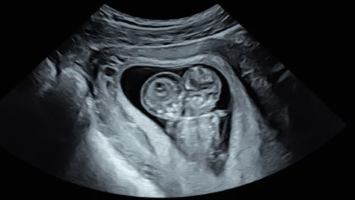

Dieser pränatale Befund hat weitreichende Konsequenzen

Eine 32-jährige Erstgravida erscheint zur Routineuntersuchung in der 11 + 1 SSW. Vorerkrankungen oder genetische Risikofaktoren können die Behandelnden nicht erkennen. Dafür aber ein sonographischer Befund, der sofort Fragen aufwirft.

e.Med Interdisziplinär Icon, Search Icon, Transvaginaler Ultraschall/© Graphicroyalty / stock.adobe.com (Symbolbild mit Fotomodellen), Glaszellentumor der Gebärmutter/© Boeker M et al. / all rights reserved Springer Medizin Verlag GmbH, Extrauteringravidität /© Tsitlakidis I et al. / all rights reserved Springer Medizin Verlag GmbH, Bilaterale ausgedehnte zylindrische Bronchiektasen/© Düsterhöft D et al. / all rights reserved Springer Medizin Verlag GmbH, CT des Uterus einer 47-Jährigen /© Rizos A et al. | all rights reserved Springer Medizin Verlag GmbH, MRT des Beckens: Uterus und Ovarialtumoren/© Hosten AK et al. / all rights reserved Springer Medizin Verlag GmbH, Digitales Blutdruckmessgerät/© Kotchakorn / Stock.adobe.com (Symbolbild mit Fotomodell), Frau tastet ihre Brust ab/© Pheelings Media / Getty Images / iStock (Symbolbild mit Fotomodell), Feten von siamesischen Zwillingen/© Zahn E et al. / all rights reserved Springer Medizin Verlag GmbH, MRT einer intrakavitären Raumforderung/© Lattermann M et al. doi.org/10.1007/s00761-025-01733-0 unter CC-BY 4.0, Aufnahme nach Resektion der Extrauteringravidität/© Antonia Jörger